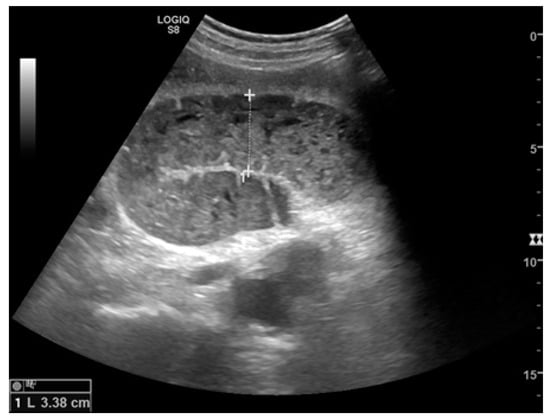

Figure 2.

A dilated small bowel loop with a caliber of more than 3 cm (dotted line) with trapped feces defines a ‘small bowel feces sign’. Bowel walls appear thin, and the folds flatten.

Small bowel dilatation is defined as bowel diameter ≥2.5 cm measured from outer wall to outer wall [12,35,37]. At an early stage of the disease, the diameter should not be considered an absolute criterion for diagnosis, and other signs must be used: the bowel loop diameter at this stage could be within the normal range, but bowel loops are fluid-filled, hyperkinetic, and with plicar hyper-representation (Figure 1a and Figure 2a) [12].

The valvulae conniventes (Kerckring valves, circular folds) are permanent folds composed of mucosa and submucosa that project into the intestinal lumen and are clearly visible in the case of fluid distension (keyboard sign) [31]. At an early stage of SBO, it is not uncommon to see the valvulae in the upstream loop appearing more numerous and closer to each other. As the occlusive state continues, the loop upstream of the obstructive fulcrum becomes weaker, bowel walls appear thin, and the folds flatten (Figure 2a and Figure 3a,b). The upstream loops more distant from the obstructive fulcrum may still present peristalsis, albeit reduced and ineffective. In complicated ileus, with the onset of vascular loop distress, the walls and valvulae become thicker and weaker due to parietal edema and venous stasis, with possible dramatic parietal necrosis and subsequent perforation (Figure 4a–d and Figure 5a,b) [12,43].